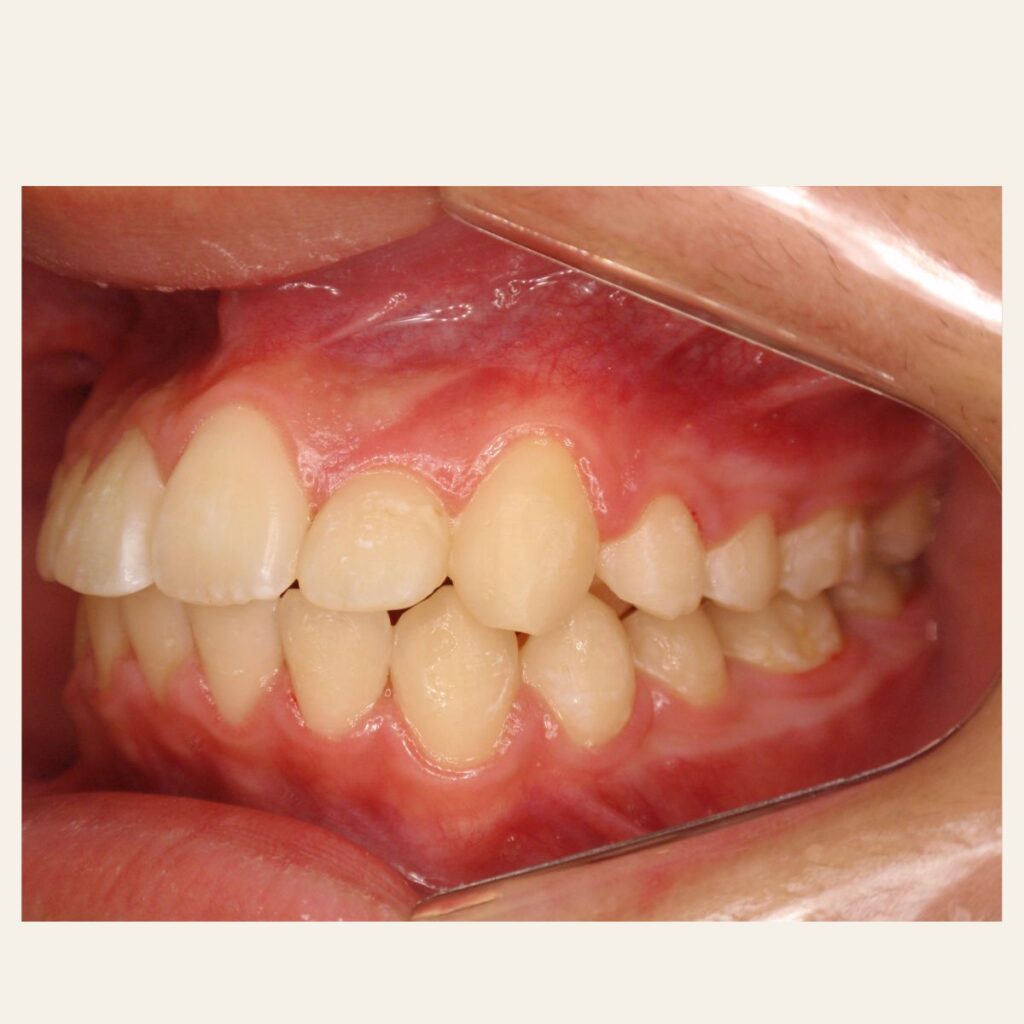

叢生の症例3(マウスピース矯正)

治療前後(BEFORE/AFTER)

| 年齢 | 10代女性、叢生、八重歯 |

| 主訴 | 八重歯、歯のガタガタ |

| 診断 | 叢生 |

| 治療方法 | 上下・マウスピース矯正(抜歯はしていません) |

| 治療期間 | 約2年 |

| 費用総額 | 1,100,000円(税込) |

| リスク・副作用 | 痛み/歯根吸収/歯肉退縮/後戻り など |

本症例では八重歯がかなり出ている叢生状態でした。

下顎前歯のガタガタも併せて治したいというご希望でした。

抜歯も検討しましたが、スキャナーによるシミュレーション、精密検査により歯列のスペースを確保しかみ合わせも意識しながら歯並びを整えるため、抜歯をしないで矯正治療を行いました。

思春期で難しいながらもマウスピース矯正で行い治療後は歯並びとかみ合わせが改善し、

見た目だけでなく歯磨きもしやすい状態になりました。